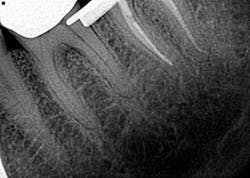

• Underfilling/overfilling

Underfilling of a canal can be caused by blockage, inadequate cleaning and shaping, ledging, and insufficient condensation pressure (figure 4). (1) Prevention is assessment via radiographs with removal and retreatment. Failure of the root canal can ensue, leading to the need for surgery or extraction.